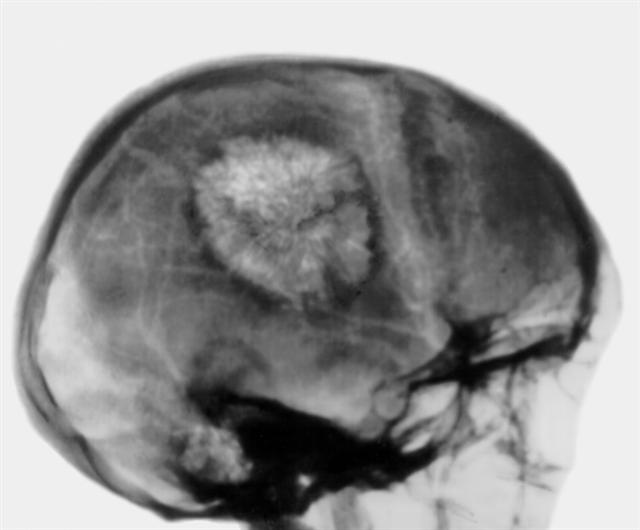

Рис. 6. Боковая рентгенограмма черепа больного при капиллярной гемангиоме теменной кости: имеется круглый очаг изменения структуры кости с типичным лучистым груботрабекулярным рисунком и краевым остеосклеротическим ободком.